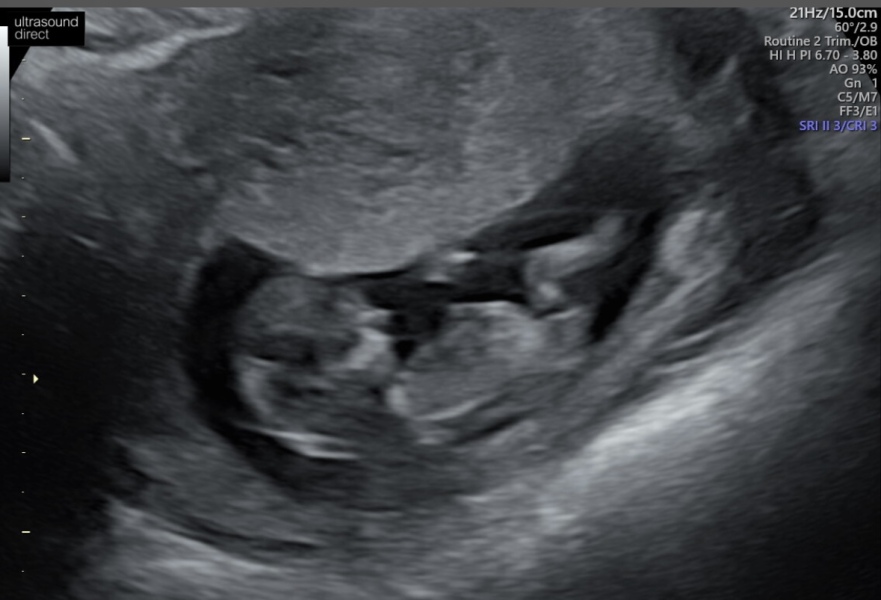

Had my scan yesterday which was supposed to be 12+5 but they said I'm 13 weeks and now due 28 aug instead of 2 sept! Will stay in this thread though 😊 Baby is doing great, such a relief!

Nausea and fatigue is subsiding now as well so feel like I can start enjoying this pregnancy!